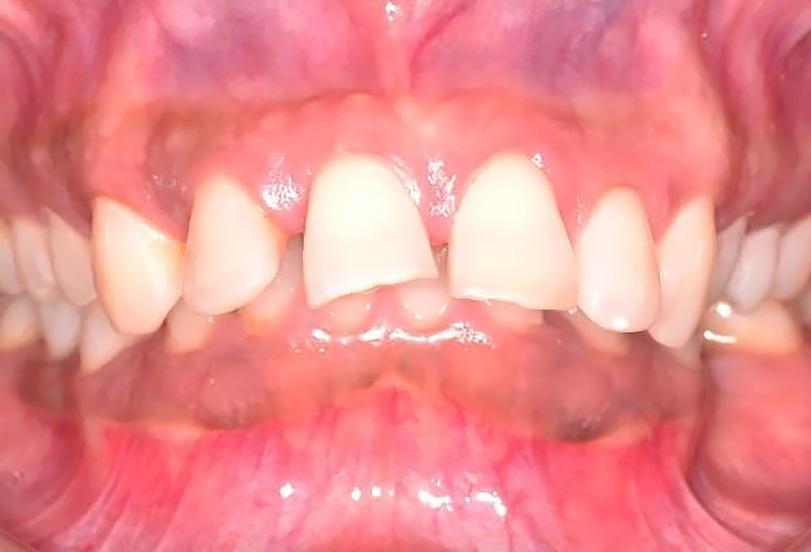

Este caso reporta los detalles de un trata miento periodontal regenerativo de los dientes 11 y 12 (sistema FDI) con movili dad severa y absceso periodontal. La pa ciente era una mujer de 27 años de edad

sin antecedentes contributivos ni aler gias conocidas, y que no estaba tomando medicamentos.

Cuando las cosas no se desarro‑ llan como estaba previsto

La paciente había comenzado un trata miento ortodóncico con un alineador transparente 6 meses antes de acudir a mi consulta. El objetivo del tratamiento orto dóntico era corregir una maloclusión cla se II de Angle con una moderada separa ción de los incisivos superiores, resalte (overjet) aumentado y proclinación de los incisivos superiores. Después de 6 meses de tratamiento, con cambios semanales de los alineadores creados por ordenador, la paciente desarrolló un absceso alrede dor del diente 12 y fue derivada a un endo doncista par drenar la lesión. Los dientes 11 y 12 se diagnosticaron como insalvables,

con profundidades de sondaje de 15 mm localizadas y movilidad de clase III. La tomografía computarizada de haz cónico (CBCT) y la radiografía periapical mostra ban pérdida de las paredes vestibular y palatina. No obstante, los dos dientes te nían un buen aporte sanguíneo, como se constató en la prueba de vitalidad pulpar. La paciente quería una segunda opinión y fue derivada a nuestra consulta.

Tratamientos periodontales y procedimientos regenerativos

El exhaustivo examen periodontal con firmó las profundidades de sondaje y la movilidad de clase III. Le explicamos los riesgos de la terapia y el pronóstico poco favorable de ambos dientes, y la paciente firmó un consentimiento informado.

Los dientes anteriores (n.º 13 23) se feru lizaron con una férula periodontal Rib bond, y la oclusión se ajustó a un contac to ligero. Se elevó un colgajo de espesor total, y el defecto se descontaminó con una combinación de láser de CO2 de 9,3 micras y EDTA al 24 %. Después de la descontaminación confirmamos un de fecto de una pared con una bolsa perio dontal intraósea de 7 mm. Injertamos el defecto con Geistlich Bio‑Oss® Collagen, que tiene una excelente capacidad para actuar como andamiaje y resulta muy útil en esta indicación.1 Después cubrimos el injerto óseo con L PRF™ para una mejor respuesta angiogénica de los tejidos.

G Radiografía periapical a los 12 meses del seguimiento. | H Hueso nuevo alrededor de los dientes 11 y 12 en la reentrada.| I Resultado final. cumplimiento del paciente, es posible re parar dientes con un pronóstico de poco favorable a insalvable. 2 4

Dientes funcionales y estéticos después de salvarlos

La paciente fue sometida a un seguimien to de 12 meses, donde se puso especial atención a la regularidad de las visitas y a la higiene oral. Al año del seguimiento y en la reentrada para mejorar el perfil del teji do blando, confirmamos que el defecto se había rellenado por completo con hueso nuevo con una adaptación estrecha a los

dientes 11 y 12. La radiografía periapical tomada en el momento confirmó las ob servaciones clínicas. Este caso destaca la importancia de realizar los diagnósticos actuales en base a los biomateriales

| A Antes del tratamiento ortodóncico. | B CBCT periapical antes del tratamiento periodontal. | C Dientes (13 y 23) ferulizados. | D Bolsa intraósea de 7 mm después de abrir el colgajo. | E Geistlich Bio-Oss® Collagen rellenando el defecto. | F Membrana L-PRF™ bioactiva cubriendo el injerto óseo. |